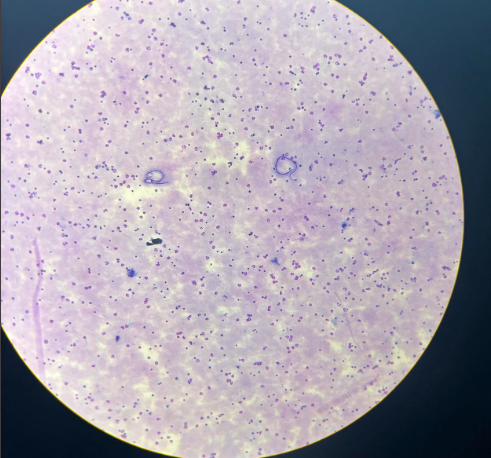

cryptosporidium parvum oocysty

cyclospora cayetanensis oocysty

cyclospora cayetanensis oocysty